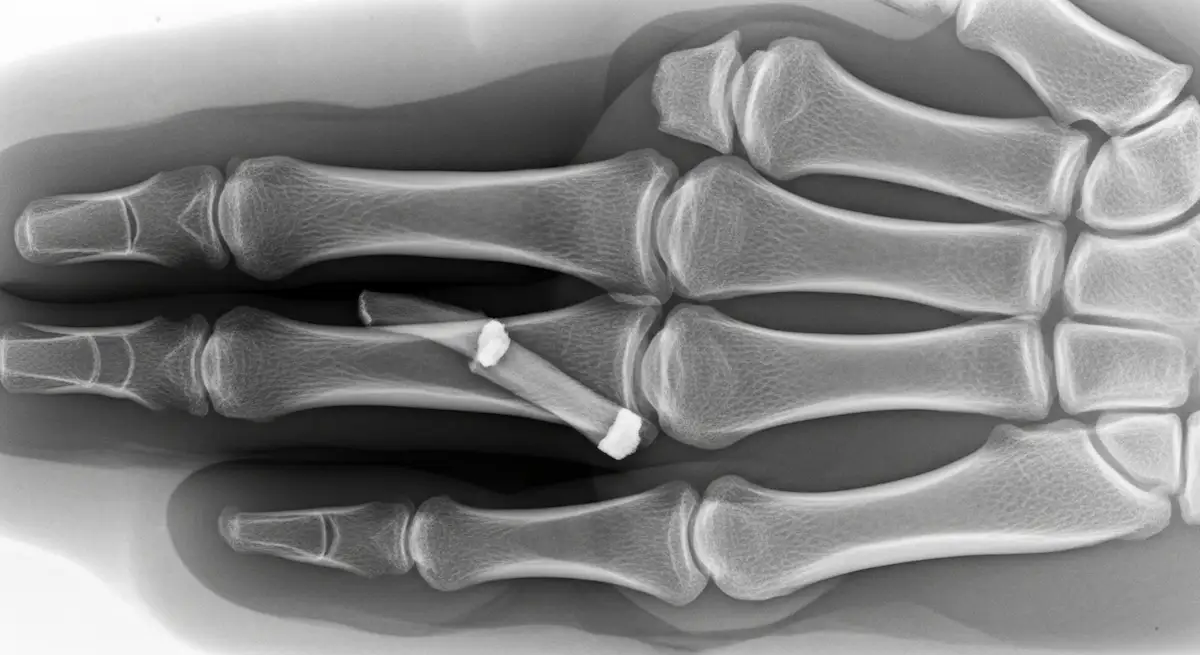

A Síndrome do Canal de Guyon acontece quando o nervo ulnar sofre compressão ao atravessar um corredor anatômico no punho. O resultado pode ser dormência, formigamento, dor e fraqueza na mão, em especial no dedo mínimo e na metade ulnar…